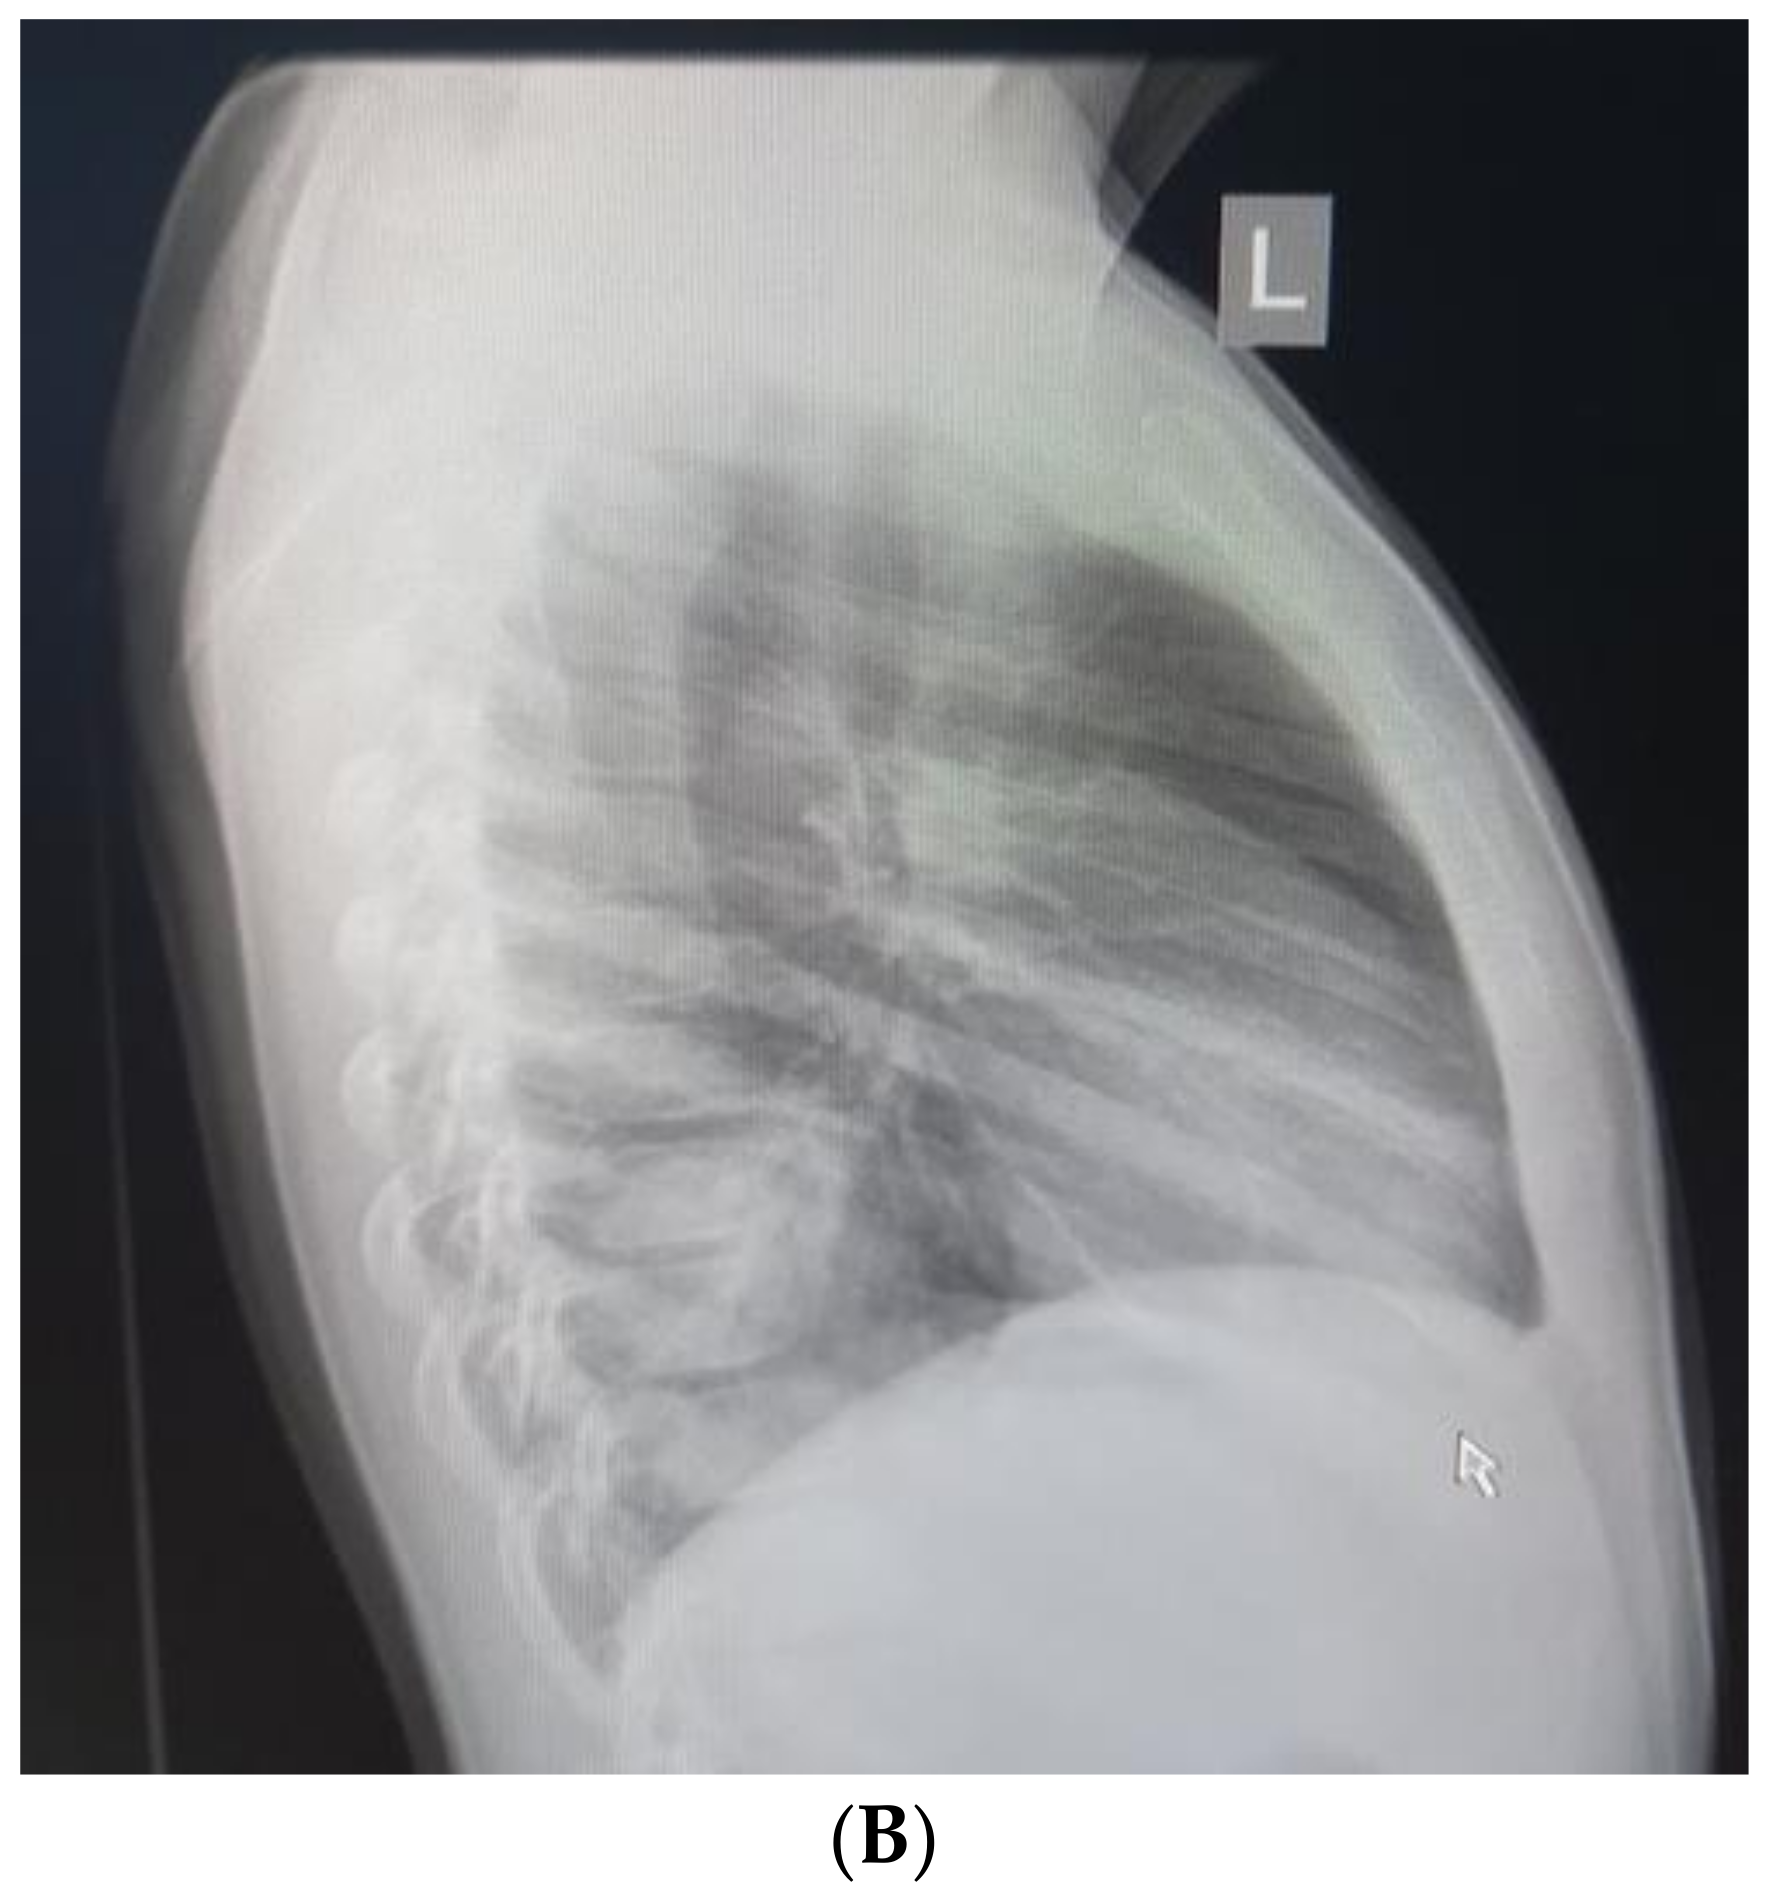

During the follow-up, the child had no complaints, and the physical examination was normal (Figure 6). The incision wounds healed primarily, and no complications were noticed. The patient recovered uneventfully. Annual physical and functional examinations of breathing will be conducted.

Figure 6. Frontal chest X-ray one month after the surgery.